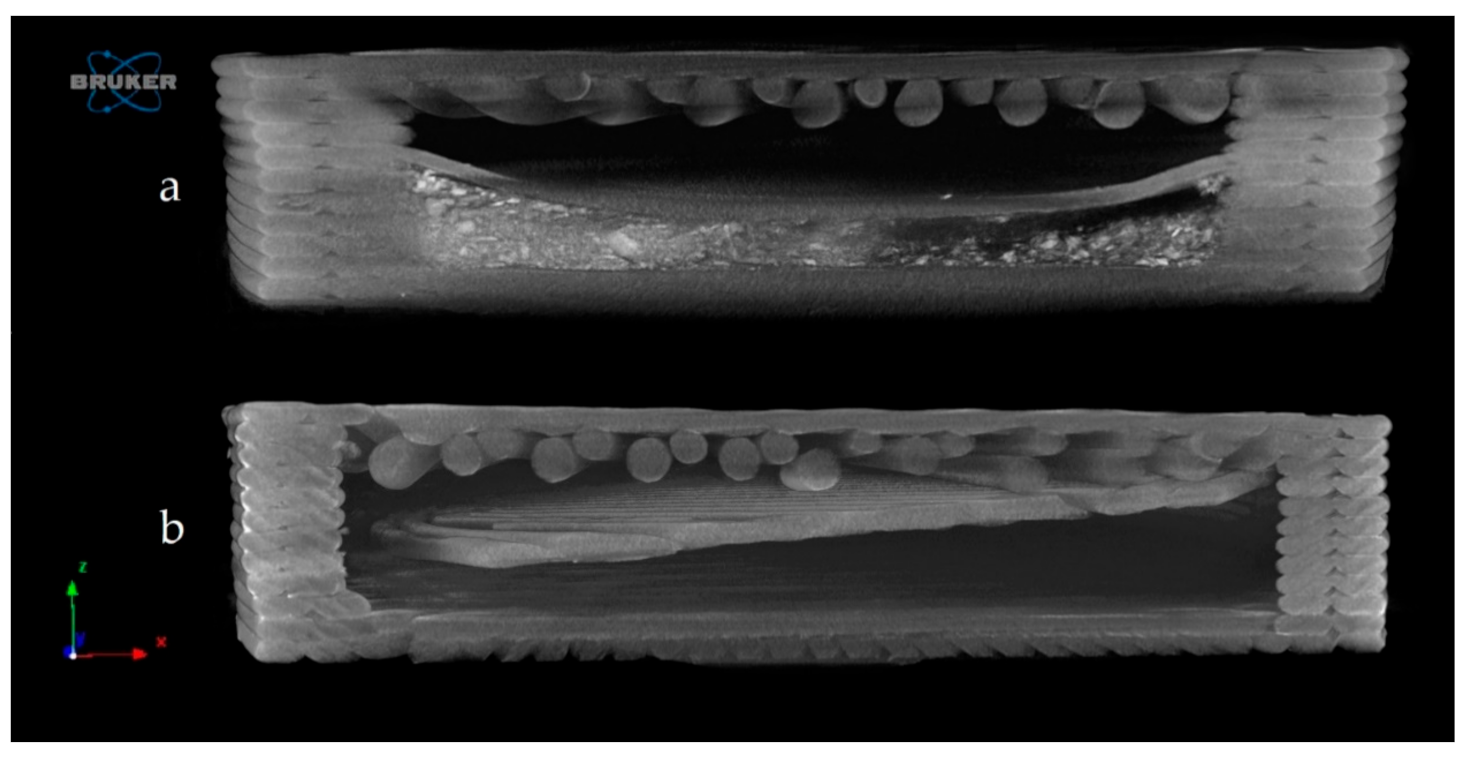

2.4.4. Microcomputed Tomography (MicroCT)

Microcomputed Tomography (MicroCT)